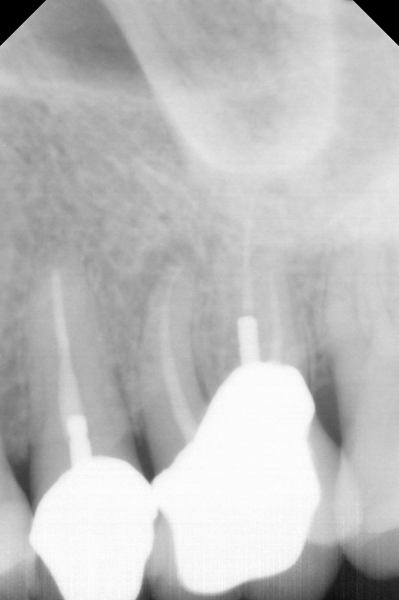

Fig 1. Preoperative radiograph showing apical bone loss.

Figure 1

Clinical procedure: If apical bone loss is present (Figure 1) a collagen/gelatin sponge (eg, Gelfoam®, Pfizer Inc., www.pfizer.com) can be placed apically so that the MTA can be delivered to the desired working length. (Any other surgical resorbable sponge would also work, such as OraPlug® [Salvin Dental Specialties, www.salvin.com], Surgifoam® [Midwest Dental, www.mwdental.com], or Surgispon® [Aegis Lifesciences, www.surgispon.com]). This is done by taking a small piece (2 mm x 2 mm) of the resorbable sponge and pushing it down to and through the root apex with an endodontic file. Once this is done, MTA is packed down the canal with a custom-fitted cone. The clinician can use a rubber stopper on the gutta-percha cone to know the exact length of MTA placed in the apical third (Figure 2). Once the apical third is sealed with 3 mm to 5 mm of MTA, the remaining coronal canal space can be back-filled using a warm gutta-percha technique (Figure 3).

Fig 15. Preoperative radiograph.

Figure 15